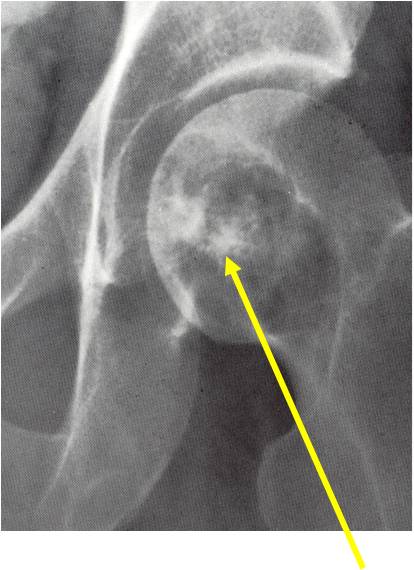

Radiographic Presentation

- Usually osteolytic, expansile lesion

- May be focally calcified

- Often a sharp interface between tumor and surrounding bone

- Sclerotic rim is uncommon

- Overlying cortex is usually thin, but intact